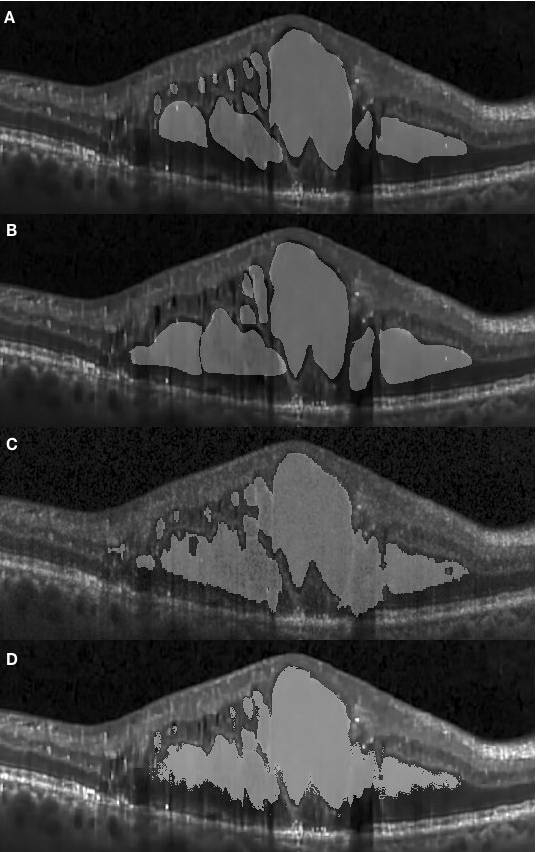

The appearance of fluid edema in OCT images is often shown with a higher contrast against surrounding tissue. Figure 4.1 (A) depicts the foveal region affected with a fluid edema. The dominant edema detaches retinal layers and small edema regions surround it sporadically. It can be seen on the framework results that the boundaries of the dominant edema are accurately segmented out, and the smaller edema on the right-hand side is also segmented individually with clear boundaries. Although two graders annotated the same fluid regions, the framework shows an improvement in terms of boundary recall. A significant inconsistency among manual segmentations on the left side of the fovea has also been observed. Because our network was trained using labels previously provided by the first grader, it is prone to be more similar to their results.

Apart from the segmentation of large areas, there are still some cases where our approach failed to segment the target region accurately. One such event occurred when small target regions were not segmented out, as shown in Fig. 4.1 (D). In this case, the small regions were affected by speckle noise and smoothing effects caused by the pre-processing resulting in the small regions being undetectable by the framework, due to their small initial size leading to them being smoothed out after several pooling layers. In another case, some target regions were only partially segmented, as shown in Fig. 4.4.